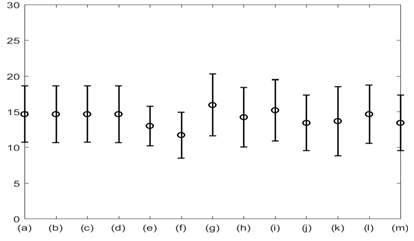

The average respiratory rate was calculated for all the signals of interest and all 12 subjects. This is plotted in Figure 8. The results shown in Figure 8 suggest that the average respiratory rate was 14 with standard error of 4 breath per minute. Subsequent analysis suggested that the overall accuracy in detecting respiratory rate using all modalities varied between 85-100% with GSR having the highest in accuracy (100%). The %Phase match for each test signal for 8 subjects is plotted in Figure 9.

Figure 8 Average respiratory rate with standard error for: (a) Lung volume change; (b) Chest wall movement; (c) GSR; baseline wonder of: (d) SCG-craniocaudal, (e) SCG-lateral, and (f) SCG-dorsoventral; amplitude modulation for: (g) SCG-craniocaudal; (h) SCG-lateral; and (i) SCG-dorsoventral; and frequency modulation for: (j) ECG, (k) SCG-craniocaudal, (l) SCG-lateral, and (m) SCG-dorsoventral signal for all 12 subjects. The average respiration rate was found to be around 14 with a standard error of 4 breath per minute.